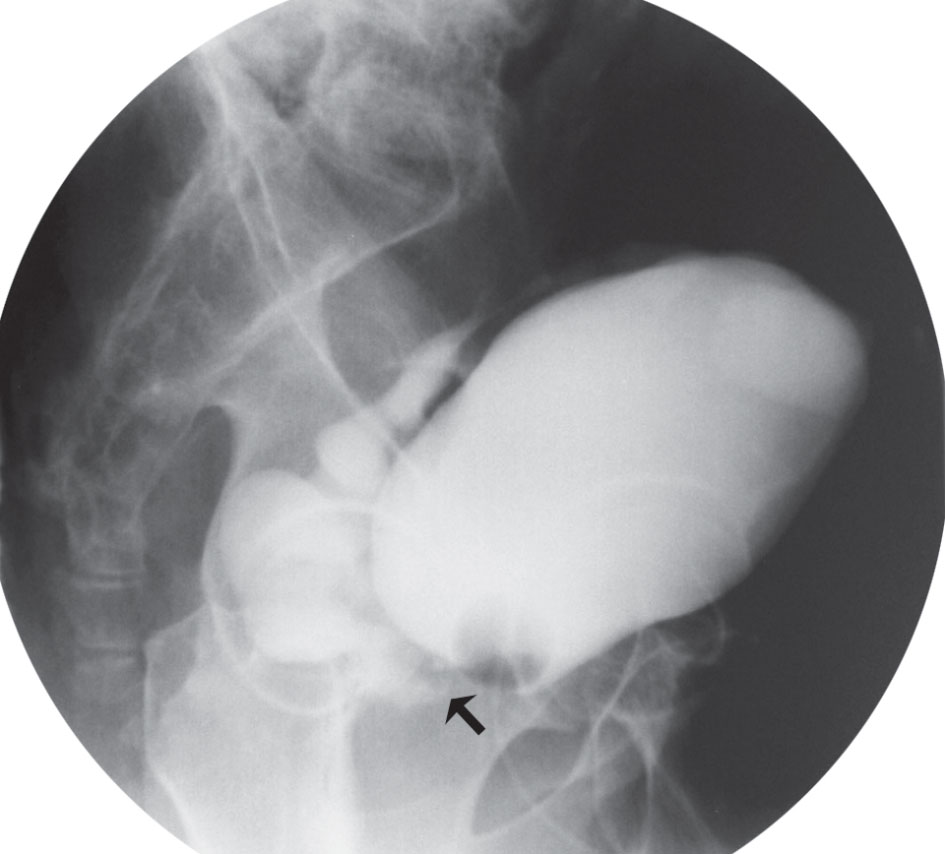

الشكل (5) أ - دسامات الإحليل الخلفي «تصوير الإحليل في أثناء التبويل». ب - دسامات الإحليل الخلفي في أثناء التنظير. |

> الموجودات الشعاعية: تصوير الإحليل والمثانة في أثناء التبويل هو أكثر الدراسات الشعاعية المتوافرة لتشخيص دسامات الإحليل الخلفي (الشكل 5-أ)، وهو يظهر الجزر المثاني الحالبي والتربق الشديد في جدار المثانة، مع تطاول الإحليل الخلفي وتوسعه، وتبارز عنق المثانة في حالات الانسداد المزمن، كما يظهر التصوير الظليل للجهاز البولي استسقاء الكلية والحالب.